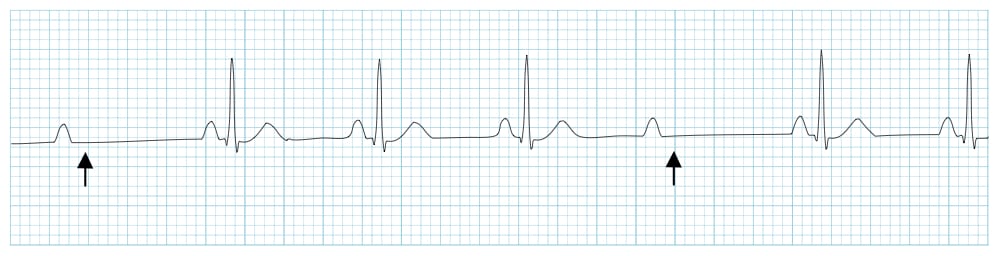

Definition of Mobitz II block (Hay Block)

A form of 2nd degree AV block in which there is intermittent non-conducted P waves without progressive prolongation of the PR interval

- The PR interval in the conducted beats remains constant

- The P waves ‘march through’ at a constant rate

- The RR interval surrounding the dropped beat(s) is an exact multiple of the preceding RR interval (e.g. double the preceding RR interval for a single dropped beat, triple for two dropped beats, etc)

ECG 1